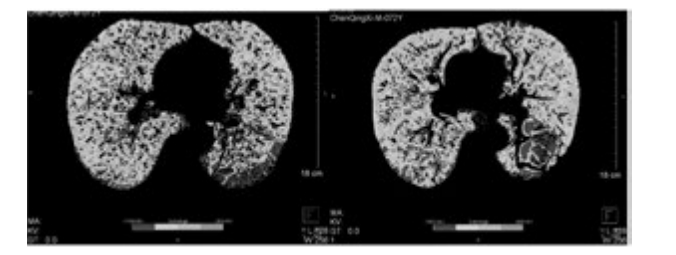

從表3、表4提示,CT 值在-1000 至-951 比例有所下降,Class4( % ) 亦明顯下降,故肺氣腫較治療前好轉(zhuǎn)。

下圖為雙源CT肺實(shí)質(zhì)分析軟件,深藍(lán)色表示CT值在-1000 至-951,治療后較治療前深藍(lán)色面積明顯縮小。